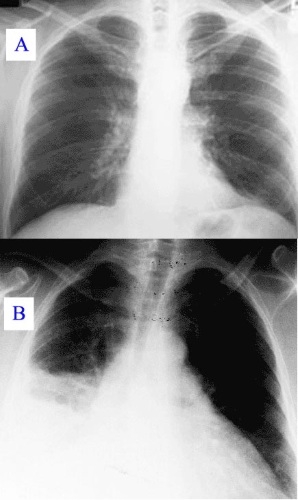

Рентгенография легких – наиболее эффективный метод диагностики, стоимость которого не превышает 300 руб.

Проводится в любом учреждении и помогает выявить локализацию очага поражения. Благодаря снимкам специалист может оценить степень поражения тканей.

Перед лечением, в процессе его проведения и после завершения важно проводить лабораторно-инструментальные обследования. Так врач понимает, эффективны ли назначаемые средства. Например, на рентгенографическом снимке выявляют затемнение легочной ткани при наличии пневмонии. Если она завершилась, паренхима легких приобретет нормальную структуру. В результате общеклинического анализа крови постепенно снизится показатель лейкоцитов и СОЭ.